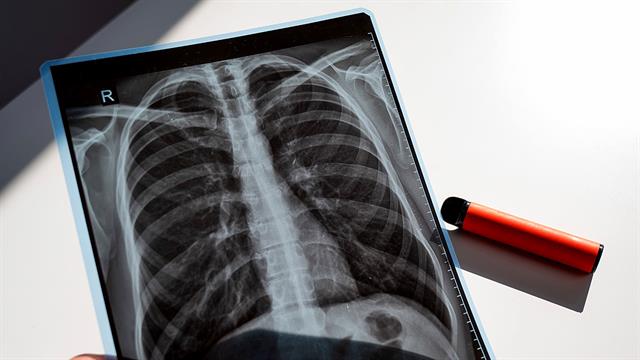

Ο καρκίνος του πνεύμονα συχνά διαγιγνώσκεται σε προχωρημένο στάδιο, όταν οι θεραπευτικές επιλογές είναι περιορισμένες. Η αξονική τομογραφία χαμηλής δόσης (LDCT) μπορεί να εντοπίσει τη νόσο νωρίτερα και μεγάλες μελέτες έχουν δείξει ότι μειώνει τη θνησιμότητα.

Γι’ αυτό και το καλοκαίρι του 2025, η Γερμανία ενέταξε τον προληπτικό έλεγχο με LDCT στο σύστημα υποχρεωτικής ασφάλισης για άτομα 50–75 ετών με υψηλή κατανάλωση καπνού, που καπνίζουν ακόμη ή έχουν διακόψει τα τελευταία δέκα χρόνια.